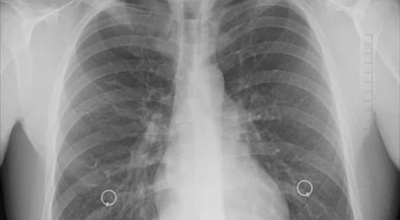

8. 갈비뼈 금간 증상 - 근육통과 금이 간 경우 차이는 거의 없습니다.

일반인이 근육통과 금이 간 경우의 차이는 거의 판별하기 힘들어요. 갈비뼈라고 하는 부분이 눈에 보이도록 붓는 것도 아니고, 멍이 들어서 아픈것도 아니기 때문이지요. 가장 정확하게 판별하는 방법은 엑스레이를 찍는 방법이지요.